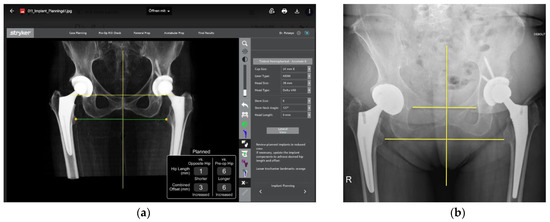

- The robotic software also enables preoperative and intraoperative visualisation of the anticipated postoperative X-rays accounting for any changes to the plan. In addition, the software allows for calculation of changes to the leg length offset compared to the preoperative and contralateral hips. In this case, the leg length was 1 mm longer compared to the opposite hip, and the combined offset was 6 mm increased compared to that preoperatively (Figure 12a,b).